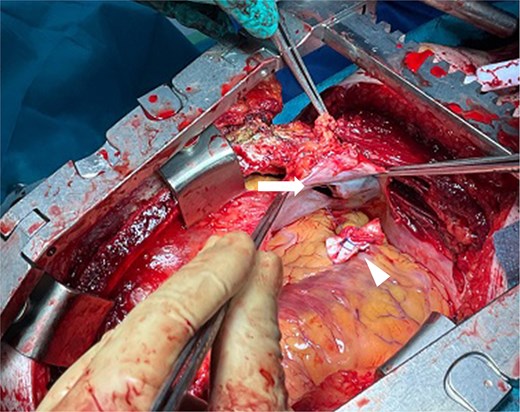

The external appearance of the wound did not clearly reflected the extent or nature of internal injury. Based on the presumptive diagnosis of intra-abdominal injury, an emergency exploratory laparotomy was performed. The initial exploration by general surgeons revealed no evidence of intra-abdominal organ damage. Given the suspicion of diaphragmatic penetration and intrathoracic hemorrhage, the cardiac surgery team proceeded with a left thoracotomy. This revealed dark, reddish fluid suggestive of pericardial hemorrhage. Suspecting obstructive shock due to cardiac tamponade, the surgical approach was converted to a median sternotomy. Upon opening the pericardium, a significant hemopericardium was identified, and active bleeding from the anterior wall of the right ventricle was successfully controlled using 3-0 polypropylene sutures with pledgets (Fig. 2). Standard chest closure and wound closure were subsequently performed, and the patient was transferred to the intensive care unit in a stable condition. The postoperative course was uneventful. Follow-up computed tomography (CT) imaging demonstrated no pericardial effusion or other complications (Fig. 3). The patient recovered favorably and was discharged home one month after surgery.

Intraoperative findings. The pruning implement had penetrated the diaphragm (arrow), resulting in right ventricular injury. Hemostasis was achieved with 3-0 polypropylene sutures reinforced with pledgets (arrowhead).